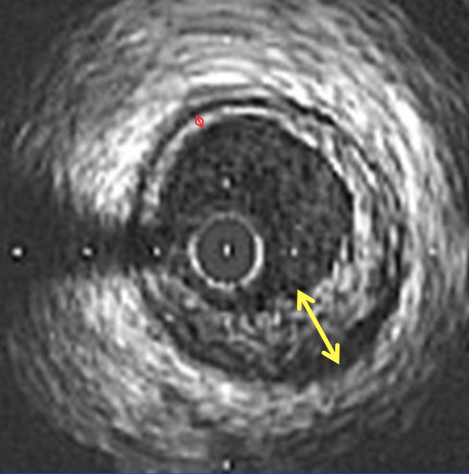

Morfología de un vaso coronario por IVUS

El vaso coronario consta de. tres capas anatómicas, de exterior a interior se ha denominado la capa adventicia, la capa elastica media y la intima o endotelio.

La capa que vamos a tomar como referencia es la capa espástica media, ya que esta. tiene una visualización fácil durante la realización del IVUS, esta es. una capa de color negro como lo muestra la figura 1.

A.- Lumen

B.- Intima

C.-EEM.- Lamina elástica media

D.- Adventicia

Medición de área de EEM.

Medición del área del ateroma.